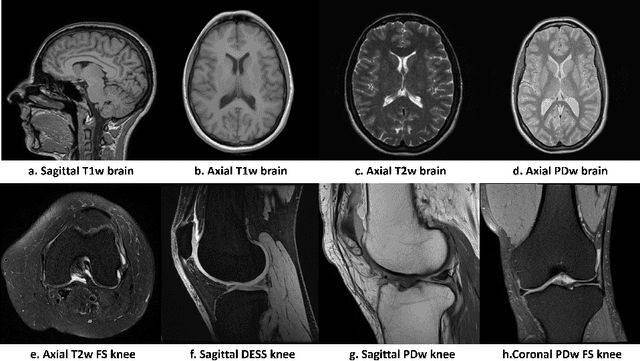

Magnetic resonance (MR) images exhibit various contrasts and appearances based on factors such as different acquisition protocols, views, manufacturers, scanning parameters, etc. This generally accessible appearance-related side information affects deep learning-based undersampled magnetic resonance imaging (MRI) reconstruction frameworks, but has been overlooked in the majority of current works. In this paper, we investigate the use of such side information as normalisation parameters in a convolutional neural network (CNN) to improve undersampled MRI reconstruction. Specifically, a Side Information-Guided Normalisation (SIGN) module, containing only few layers, is proposed to efficiently encode the side information and output the normalisation parameters. We examine the effectiveness of such a module on two popular reconstruction architectures, D5C5 and OUCR. The experimental results on both brain and knee images under various acceleration rates demonstrate that the proposed method improves on its corresponding baseline architectures with a significant margin.